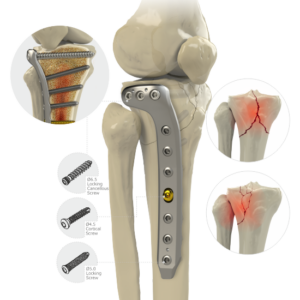

Large Fragment Locking Plate System

Locking Proximal Lateral Tibial L Plate